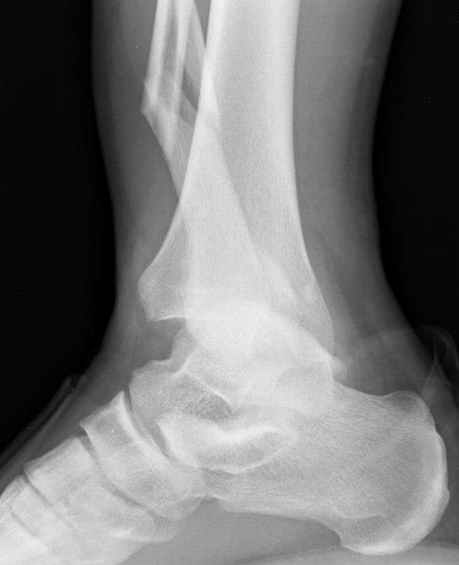

>На сделанных у нас снимках видно, что не все благополучно...

Неравномерность суставной щели может быть связана с разрывом глубокой порции дельтовидной связки и ротацией м/берцовой кости за счет поврежденных структур синдесмоза(репозиция ее на уровне перелома как-будто удовлетворительная).

По моему мнению,ассиметрия суставной щели обусловлена импрессией медиальной части суставной поверхности б/б кости. Да, позиционный винт здесь не лишен, но через 4 недели целесообразность его проведения сомнительна, брейс, ограничение осевой нагрузки достаточно.Есть еще деонтологические аспекты повторной операции, не все так плохо выполнено предыдущим доктором!

Импрессия медиальной части суставной поверхности бывает при супинационном механизме перелома лодыжек (тип А по классификации АО). Здесь механизм пронациия+наружная ротация (тип С, синдесмоз и межкостная мебрана повреждены),

перелом медиальной лодыжки отрывной, при этом в 20-30% бывает повреждение дельтовидной связки.

Клиновидность щели сустава следствие повреждения дельты, невосстановления длины малоберцовой или (хотел сказать "установки в гипсе", но оного, вроде,

Мое мнение, что никакой ротации малоберцовой кости здесь нет и синдесмоз тоже впорядке. Все дело в некачественно репозиции медиального мыщелка. Скорее всего его или немного ротировали при операции или сместили латерально. Более склонен ко второму варианту.

Конечно, компьютерный томограф более информативный метод, но с помощью недорогого обычного стандартного в нейтральном положении стопы: прямого, бокового и косой (ankle mortise) ренгенологического метода можно получить полную информацию о повреждении голеностопного сустава, а сравнительный снимок с другой стороны подтвердить наличие повреждения.

При реконструкции голеностопа, о важности восстановления длины малоберцовой для профилактики пост травматического артроза разбирали в предыдущих дискуссиях. Нарушенную биомеханику голеностопа без восстановления длины малоберцовой, не восстановить только швом медиальной связки.

Расширенная медиальная щель более чем на 4 мм и укорочение малоберцовой более чем 2 мм, а перелом заднего края большеберцовой смещения более 2мм с вовлечением 30% поверхности сустава, считается отходом от нормы голеностопного сустава, и подлежит к оперативному вмещательству.